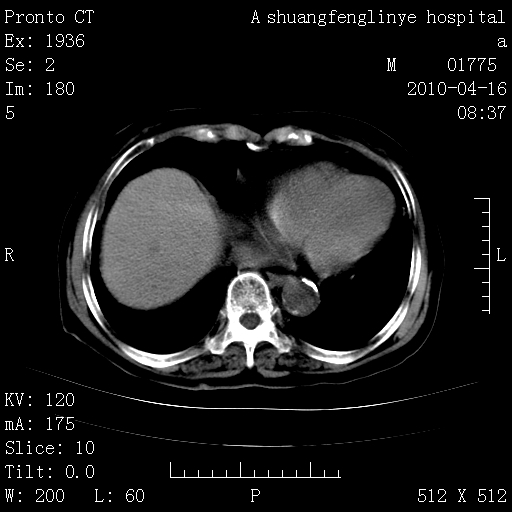

标题: CT25784:咳痰、请会诊!结核?

陈旧性结核,胃腔扩大,脾脏受压后移

老年肺间质纤维化,肺动脉高压-----肺心病。

慢支肺气肿,左上陈旧性结核,主动脉冠脉钙化

典型 夹层动脉瘤。 内膜瓣钙化移位

1)左肺上叶结核(纤维、增殖病灶)。2)冠状动脉及主动脉钙化。

1)左肺上叶结核(纤维、增殖病灶)。2)冠状动脉及主动脉钙化。肺动脉高压